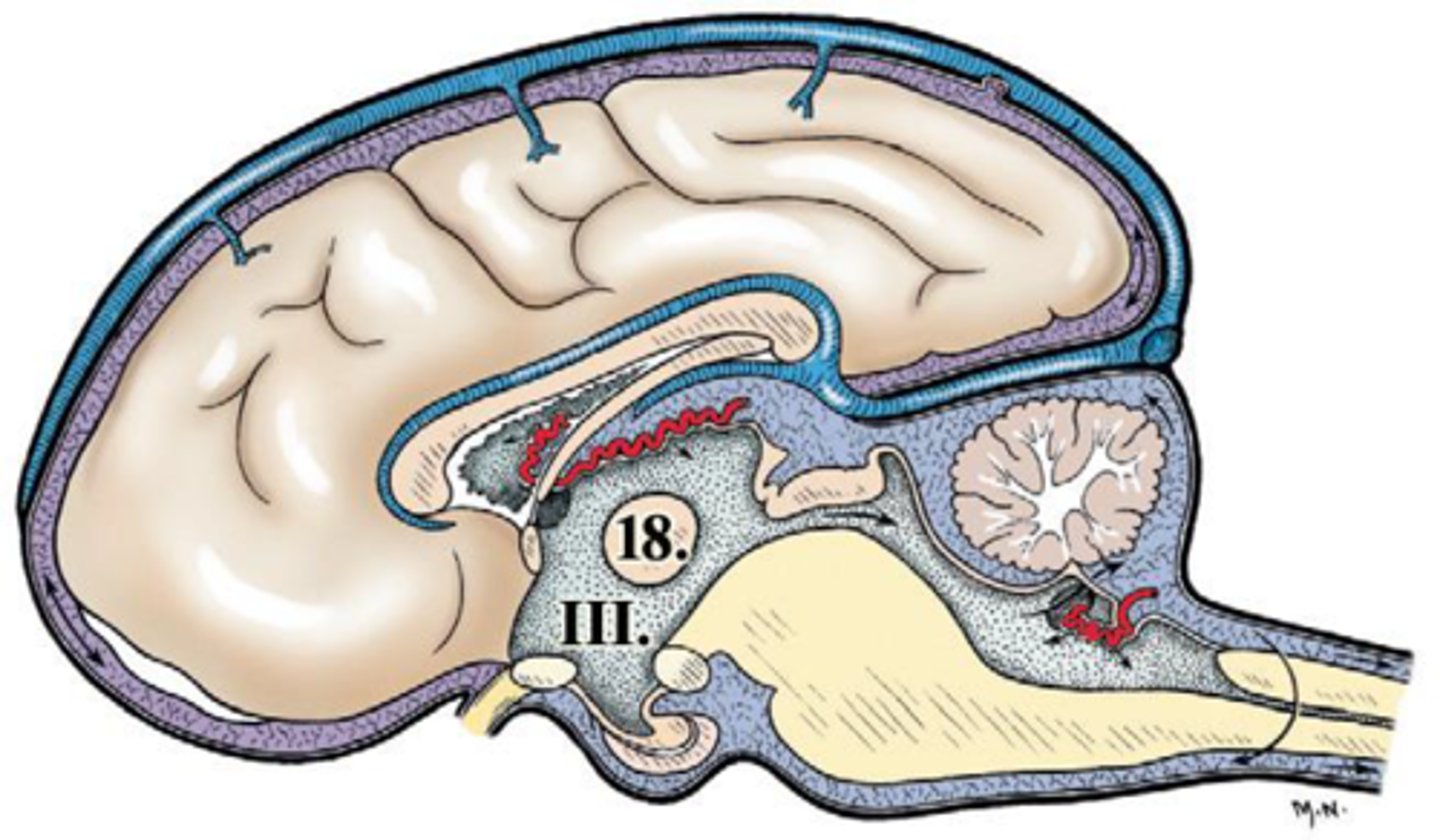

ventriculus tertius

III

adhesio interthalamica

18